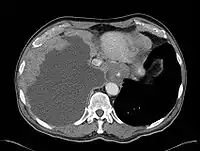

< Radiation Oncology < Mesothelioma

Mesothelioma Overview